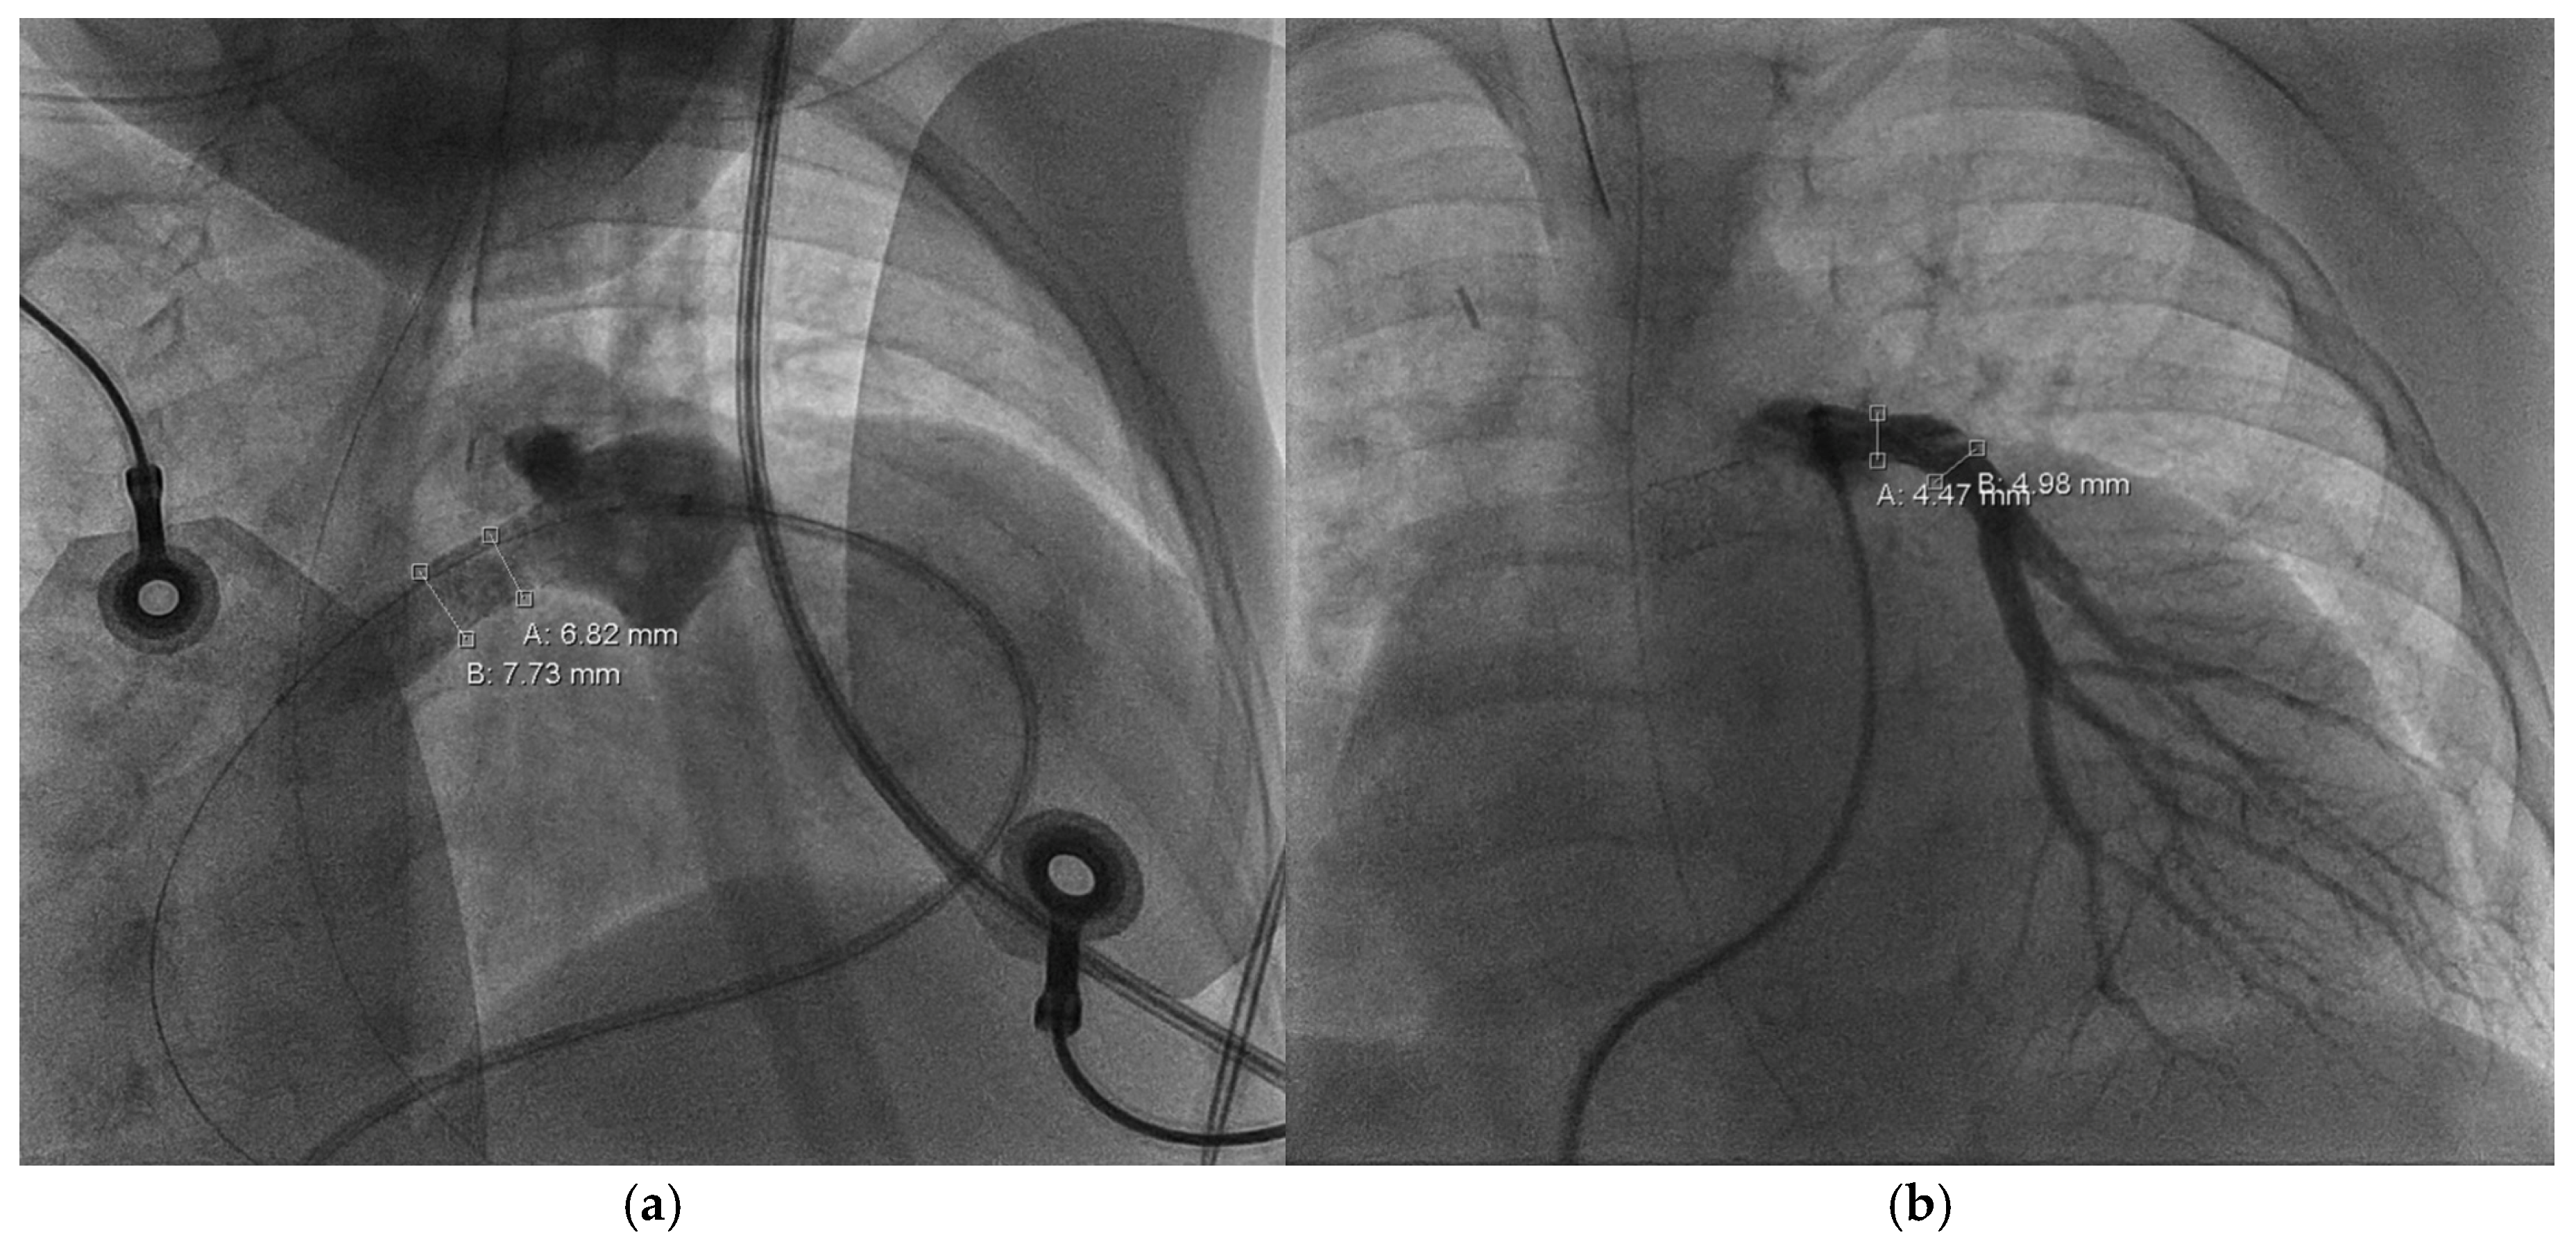

Follow-up in the third month of life confirmed preserved LV function (FS = 38%) and bidirectional shunt flow across the Starnes patch with an estimated RV pressure of 10 mmHg and a well-perfused AP shunt with a stable gradient of 4 m/s. Both hypoplastic PAs were perfused (LPA > RPA; LPA = 4.9 mm, RPA = 2.3 mm). Due to increasing LPA/RPA imbalance and filiform, laminar RPA flow, sectional imaging was performed via magnetic resonance imaging (MRI). Because of the bilaterally small-caliber PAs without dilatable local stenosis and insufficient RV volume for biventricular correction, we opted for interventional dilation of the AP shunt clip. As part of the corresponding cardiac catheterization (CC) at the beginning of the fourth month of life, several balloon dilatations of the AP shunt in clip position to a maximum of 4 mm were performed. The PAs appeared to be more prominent on CC than depicted in MRI (LPA = 5 mm, z = −0.2; RPA = 4.3 mm, z = −1.1; see Figure 3).

Figure 3. Cardiac catheterization, a.p.; measurement of the left pulmonary artery (=B: 5.07 mm) and right pulmonary artery (=A: 4.35 mm) diameter.